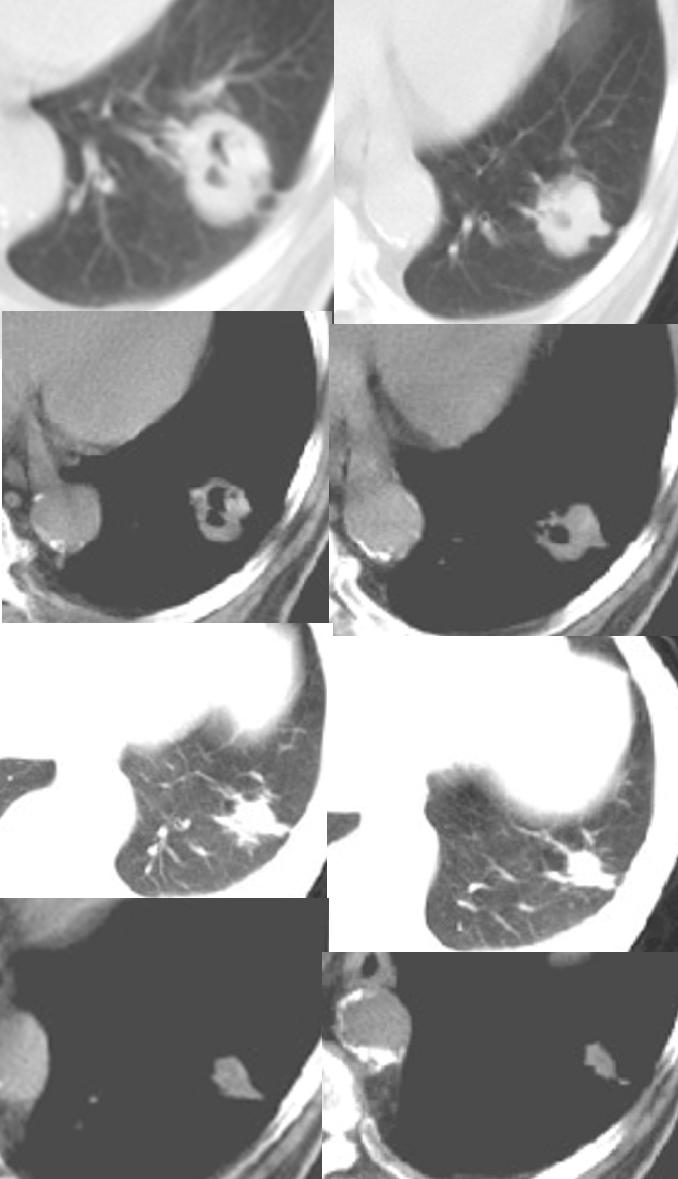

以下是引用狙击手在2008-6-26 20:16:00的发言:[br]上腹部除了胆囊大一点,其余未见明显异常,肺尖部见纤维条索样影,左肺下叶见空洞样占位,壁较厚,临近胸膜见牵拉,周围未见卫星灶,考虑:1:左下肺周围性肺癌;2:肺尖部陈旧性结合灶。

以下是引用liuqiang在2008-6-26 21:11:00的发言:[br]上腹部除了胆囊大一点,其余未见明显异常,肺尖部见纤维条索样影,左肺下叶见空洞样占位,壁较厚,临近胸膜见牵拉,周围未见卫星灶,考虑:1:左下肺周围性肺癌;2:肺尖部陈旧性j结核灶。